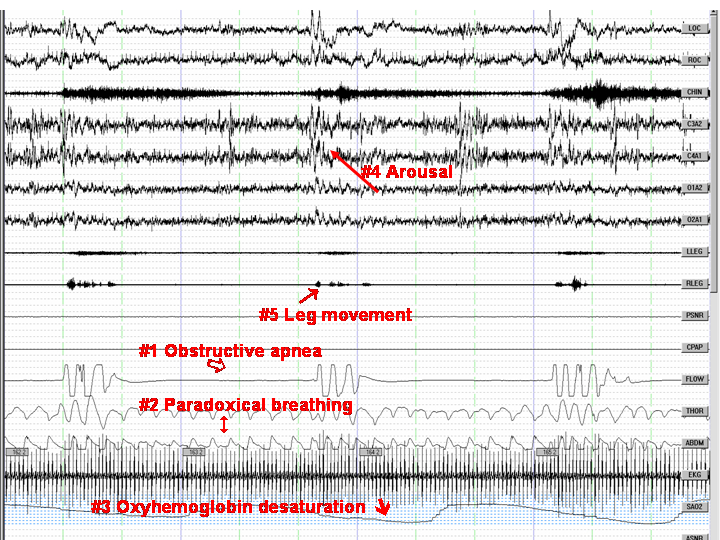

The figure shows four 30-second epochs of sleep from an adult sleep study. Shown are two complete obstructive apneas with associated events as below.

#1: obstructive apneas

#2: paradoxical movement of the thorax and abdomen in the effort channels

#3: oxyhemoglobin desaturation

#4: arousal

#5: leg movement

Abbreviations: LOC: left oculogram; ROC: right oculogram; CHIN: chin EMG; C3A2, C4A1: central EEG leads; O1A2, O2A1: occipital EEG leads; LLEG: left leg EMG; RLEG: right leg EMG; PSNR: snoring channel; CPAP: CPAP flow channel; FLOW: nasal pressure flow channel; THOR: thorax effort channel; ABDM: abdominal effort channel; EKG: electrocardiogram; SAO2: oxygen saturation channel.

Source: overnight polysomnography Species: human